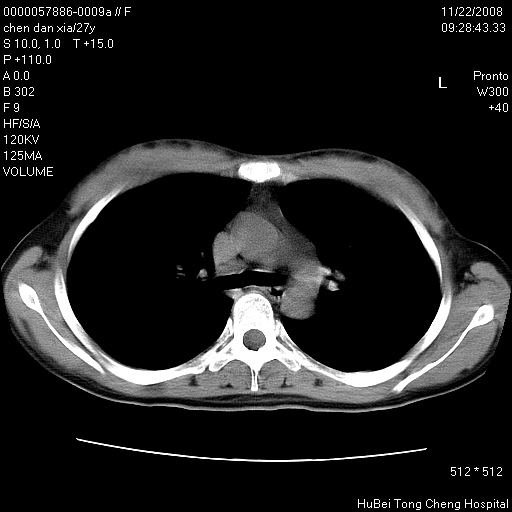

标题: CT16752:F,27Y。发热咳嗽20余天,伴盗汗。 [打印本页]

标题: CT16752:F,27Y。发热咳嗽20余天,伴盗汗。

气管前腔静脉后淋巴结肿大 右肺门纹理模糊

淋巴结核?

右下肺见片絮状影,两肺野内分布不均的小结节影,结核并肺内播散可能性大,建议结合实验室检查 .

右下肺纹理模糊;纵隔可见肿大淋巴节;右心缘旁结节,边缘光滑,纵隔窗病变范围较肺窗明显小,首先考虑右下肺结核,不排外淋巴瘤

下肺结节,结节内钙化,肺门纵隔淋巴肿大 结核可能性大

1)考虑两肺感染性病变。2)纵隔淋巴结肿大。